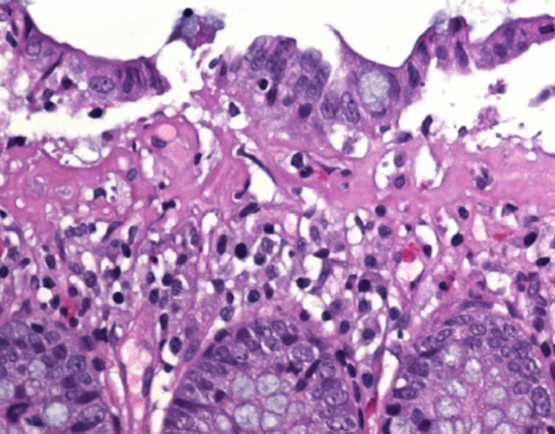

Bedöm biopsin

Vad ser du på den uppförstorade biopsin?